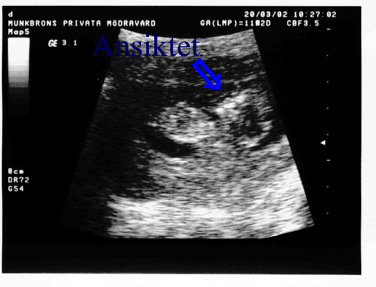

Ett barn upptäcks Mage Ultra pictures

Här är en bild på ultraljudet efter 12 veckor. Av någon outgrundlig orsak blev de mycket tydligare än de efter 18.